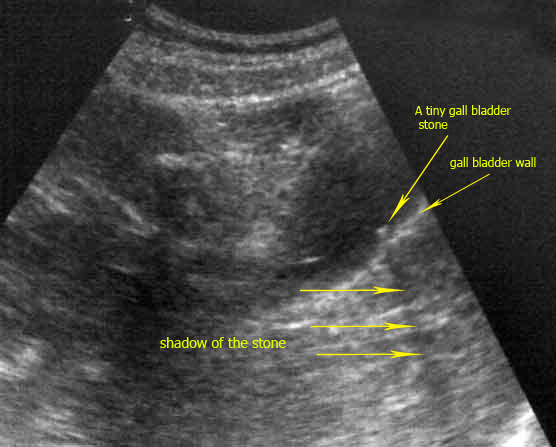

Looking carefully:

The pain is the hero in this situation which was severe and distressing

and of acute onset 2 months after having childbirth, so it is worthwhile

to re-check the gall bladder and the biliary tract meticulously so that

no thing to be missed even small.

Now you can re-check the photo to see the very small stone which is a

strong indicator for the others that could be one or more of them were

passing through the biliary tract giving rise to both the severe

resistant pain and the disturbed liver functions .